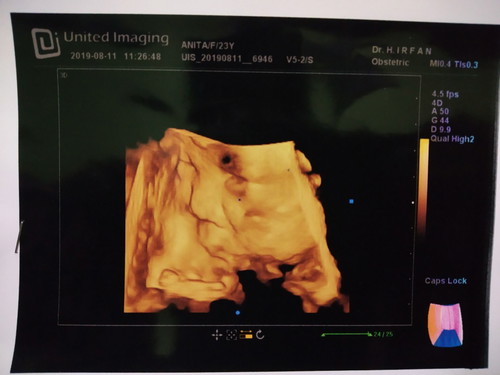

hasil usg 34mgg

bun mau tanya, ini hasil usg 34mgg dan minggu skrg 35mgg. minggu ini baru ngeuh kalo di hasil usg ada yg hitam2 gtu di area wajahnya, ada yg bisa bantu jelaskan bun? :( soalnya ini kehamilan anak pertama..